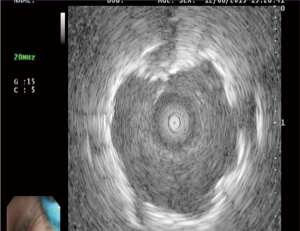

ENB is an effective and safe procedure. Peripheral lesions in the outer third of the chest less than 2 cm in diameter have a diagnostic yield of only 14% using conventional flexible bronchoscopy (2). Utilization of ENB in conjunction with use of a radial endobronchial ultrasound (R-EBUS) results in a yield of approximately 88% (Figure 2) (3). Additionally, the safety of the procedure is excellent, with a pneumothorax rate between 0–10% (4,5). Alternative options for sampling peripheral lung nodules include TTNA and surgical biopsy. Transthoracic needle aspiration is effective, with a yield of approximately 80%, the risk of pneumothorax associated with TTNA range anywhere from 5% to 64% (6-12).